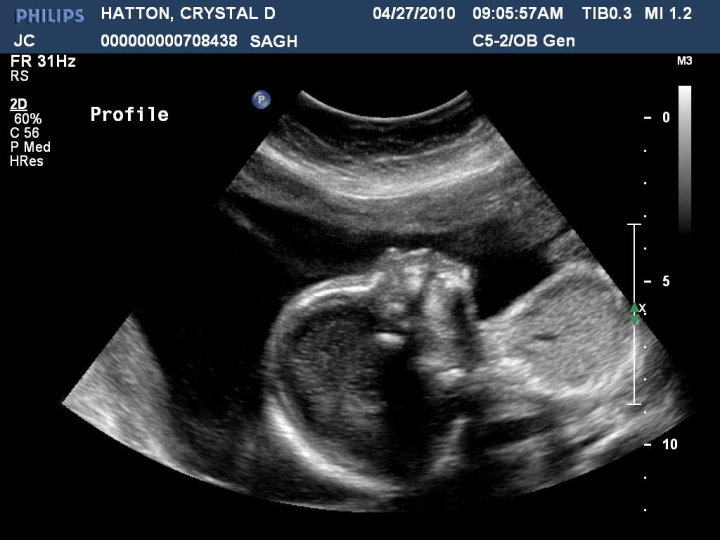

Here is the handsome little guy! :) Name tbd...